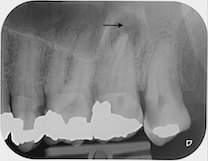

Fallbeispiele

Zum Vergrössern klicken